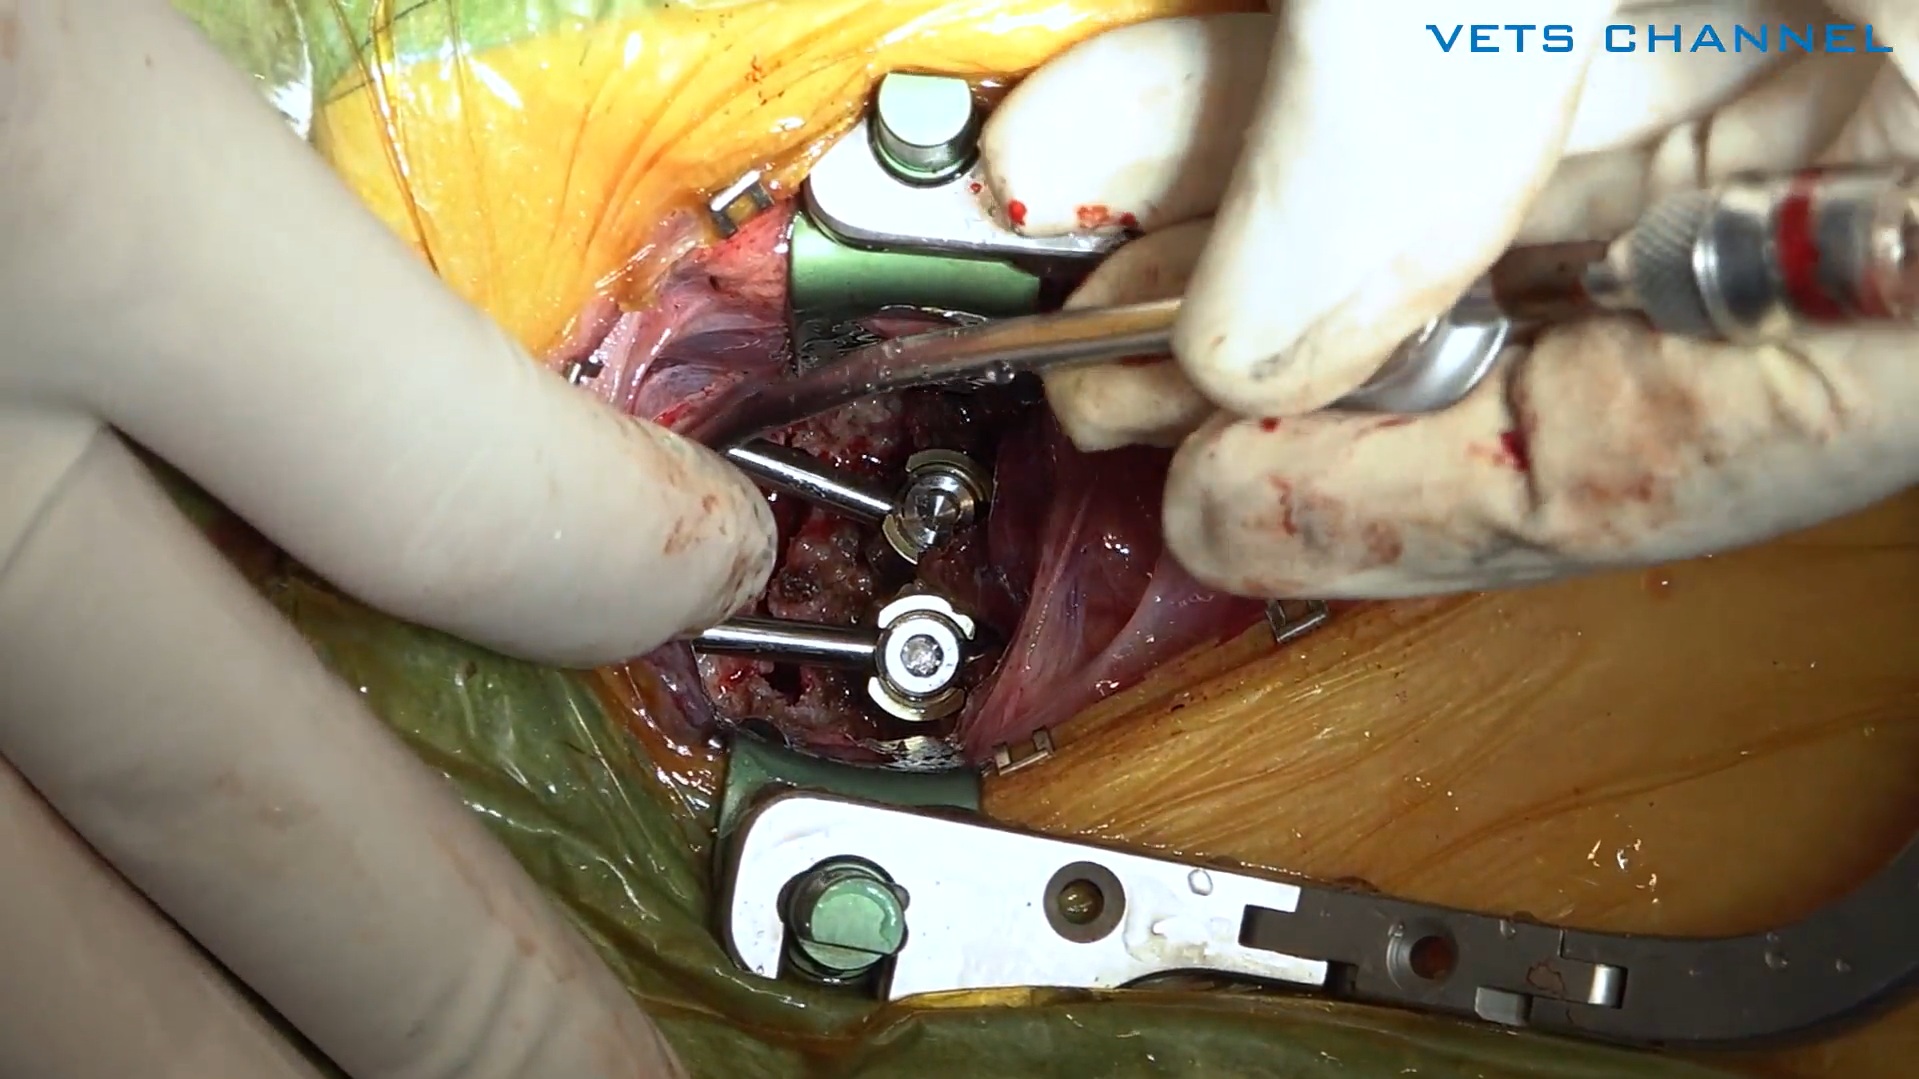

Dr.神志那 Neuro Surgery 環軸固定 スクリューロッド法

- OPE

- 脳神経外科

- 犬

神志那 弘明先生(Kyoto AR 動物高度医療センター)

42分

2025/10/31

Dr.神志那 Neuro Surgery 環軸固定 スクリューロッド法

- OPE

- 脳神経外科

- 犬

神志那 弘明先生(Kyoto AR 動物高度医療センター)

42分

2025/10/31